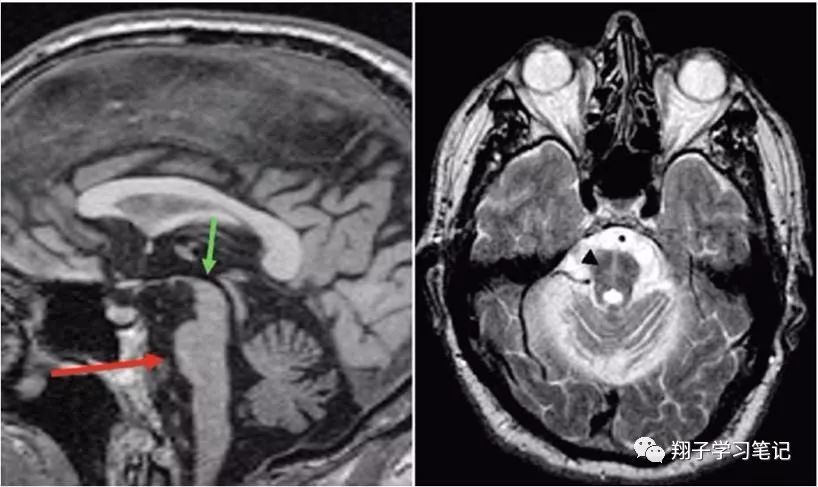

影像表现:脑桥可见“十字交叉征”,中脑、脑桥、小脑萎缩。

在MSA-C小脑亚型:T1加权MRI:以桥脑和小脑萎缩为主。在T2加权MRI:十字面包征被认为是MSA-C的一个有用的临床标志物。但实际上该影像征象可能发生在其他疾病的晚期:如:中枢神经系统血管炎、副肿瘤综合征和脊髓小脑性共济失调(SCA)。

下图显示MSA的病例:矢状面中部图像(左侧)显示脑桥变平,体积减少(红色箭头),横向T2加权图像(右侧):十字包头征(箭头)。注意正常的中脑外观(绿色箭头),与PSP(中脑扁平)相反。